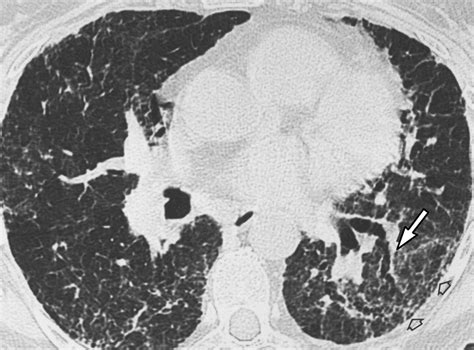

• Chest X-ray or CT scan

• bird fancier lung x ray

• bird fancier's lung radiology